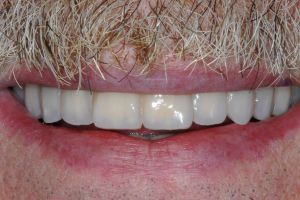

Gli impianti sono stati posizionati in punti strategici per ottenere due risultati fondamentali: far uscire i denti direttamente dalla gengiva naturale di Marco e chiudere gli spazi antiestetici che si erano creati a causa della malattia.

Grazie a un approccio mini-invasivo, Marco ha ritrovato un sorriso stabile e sicuro, con denti fissi che emergono in modo armonioso dalle sue gengive naturali, rispettando a pieno le sue richieste estetiche e funzionali.